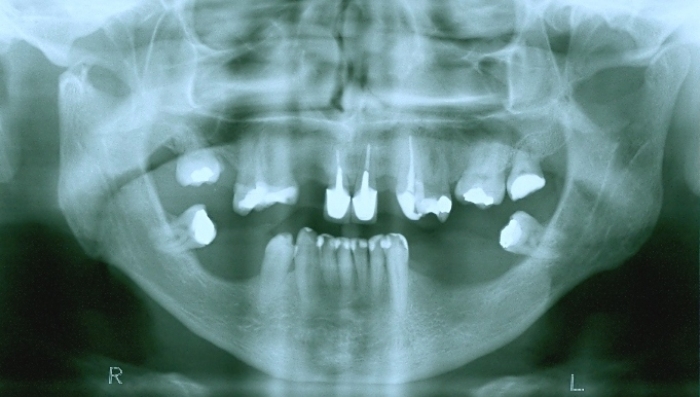

Raio - x inicial em 2009 - Clínica Cliniface

Raio - x inicial em 2009